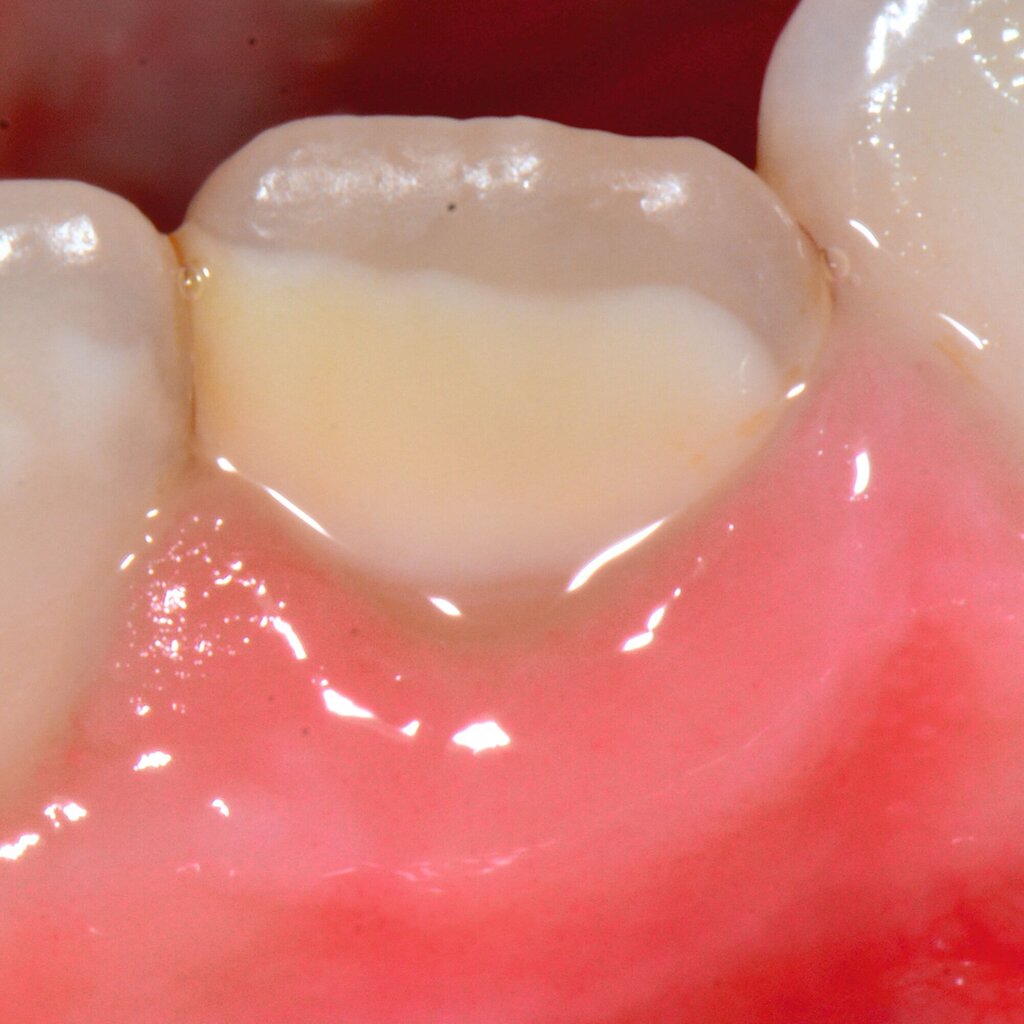

Das klinische Erscheinungsbild an bleibenden Zähnen zeigt typischerweise weißlich-gelbe bis gelblich-braune Opazitäten, die zumindest in einigen Bereichen durch eine scharfe Abgrenzung (engl.:„demarcated opacities“) zum gesunden Zahnschmelz charakterisiert sind (Abbildungen 3 und 4). Die abgegrenzten Hypomineralisationen befinden sich mehrheitlich im Bereich der inzisalen Kronenhälfte unabhängig von dem Auftreten an Front- oder Seitenzähnen. Die Ausprägung am Zahn kann dabei auf einzelne Areale oder Höcker begrenzt sein.

Für die Dokumentation und Klassifikation der MIH wurden verschiedene Systeme vorgeschlagen. Als historisch und veraltet gilt der (modifizierte) DDE-Index. Demgegenüber haben die Kriterien der EAPD – abgegrenzte Opazitäten (Abbildung 3 und 4), Schmelzeinbrüche (Abbildung 5), atypische Restaurationen (Abbildung 6) – mittlerweile die weiteste Verbreitung gefunden. Diese wurden 2003 erstmals zur Beschreibung der MIH auf empirischer Basis publiziert [Weerheijm et al., 2003] und den Jahren 2010 und 2022 im Rahmen der damaligen MIH-Workshops bestätigt [Lygidakis et al., 2010; 2022].